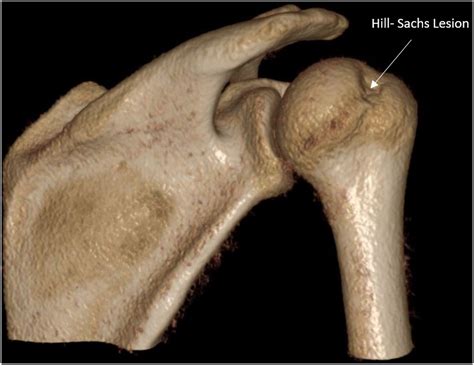

A Hill Sachs Lesion is a specific type of injury that occurs in the shoulder joint. It is characterized by a compression fracture of the humeral head, which is the ball part of the shoulder joint. This injury typically results from a shoulder dislocation, where the humeral head is forced out of its socket, the glenoid. When the shoulder is reduced back into place, the humeral head can impact the rim of the glenoid, causing a compression fracture. This fracture is known as a Hill Sachs Lesion, named after the doctors who first described it, Dr. Harold Hill and Dr. Maurice Sachs.

• Imaging studies: X-rays, MRI, or CT scans may be used to visualize the shoulder joint and confirm the presence of a Hill Sachs Lesion. These imaging studies can also help determine the size and location of the lesion, which is important for treatment planning.